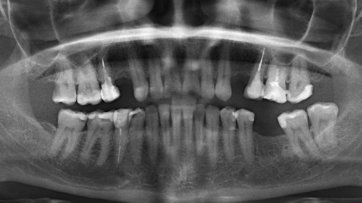

Около 3-х лет назад мне удалили нервы из верхней правой шестерки. Спустя 2 года воспалились корни, т.е. около 9 месяцев назад перелечивали корни, поставили коронку. Месяц назад зуб снова заболел, оказалось воспаление под корнем.

Хотелось бы узнать, действительно ли есть воспаление? И вообще в целом ситуацию насчет этого зуба, какое лечение следует предпринять? Есть 2 панорамных снимка.

Действительно, в зубе имеется хронический воспалительный процесс, причина — некачественное лечение каналов. Зуб будет лечиться в несколько посещений, и при квалифицированном подходе его вполне можно спасти.